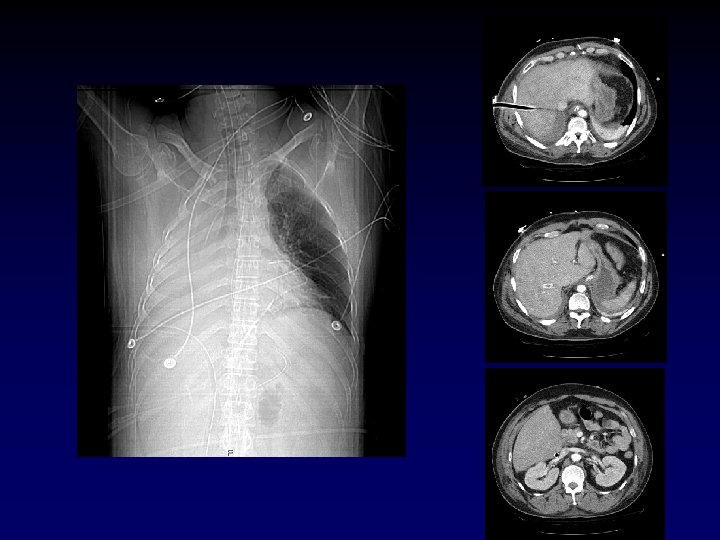

Case Presentation • Now that the chest tube is draining the hemopneumothorax, the patient’s pressure drops to 60/palp • Help? • The patient has bilateral track marks from history of IVDA.

Central Venous Access • Indications – CVP monitoring – TPN – Long-term infusion of drugs – Inotropic agents – Hemodialysis – Poor peripheral access

Central Venous Access • Vein sites – Femoral – Subclavian – Internal jugular • Contraindications – Vein thrombosis – Coagulopathy or thrombocytopenia

Case Presentation • Now with a femoral cordis in place, the patient receives 2 liters of LR with an improvement in vitals. He has 800 cc of blood drained from his left chest. • Is he adequately resuscitated? Over? Under?